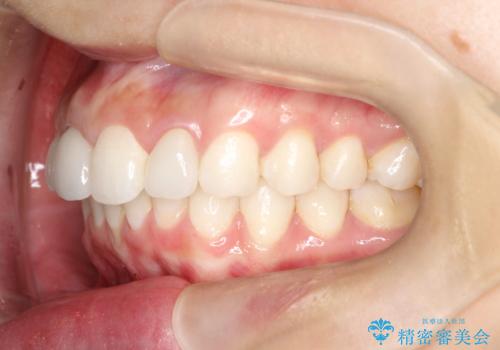

後戻りした歯並びをきれいにしたい

- ワイヤーで矯正した後戻りをマウスピースで治そうとしたが、使えなかったため再度ワイヤー矯正希望で来院されました。

装置はハーフリンガルを選択しています。

矯正としてはマウスピースでできましたが、患者さんの希望でワイヤー(ハーフリンガル)で矯正を行いました。

右下1が歯肉退縮していたため、アーチを拡げないように歯と歯の間を削って隙間をあけて並べています。